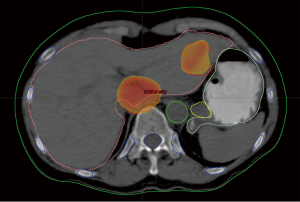

Case discussion 1 (Figure 5)

A 67-year-old woman with a history of adenocarcinoma of the sigmoid colon status post sigmoidectomy presents with new onset fatigue and a rise in carcinoembryonic antigen (CEA). A CT of the chest, abdomen and pelvis, reveals new liver lesions in segments I and V, and a CT guided biopsy of the segment V reveals adenocarcinoma. As the patient had tolerated any of her chemotherapy with difficulty, medical oncology recommended liver-directed therapy. Interventional radiology reviewed her films but did not this that was an optimal situation for RFA due to possible heat sink of the central lesion and possible gastric injury for the segment V lesion. Given her low volume of disease, chemo- or radio-embolization was not warranted. Therefore, SBRT was proposed and delivered to the patient.